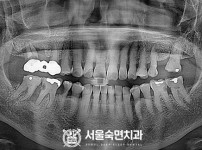

임플란트-전후사진1